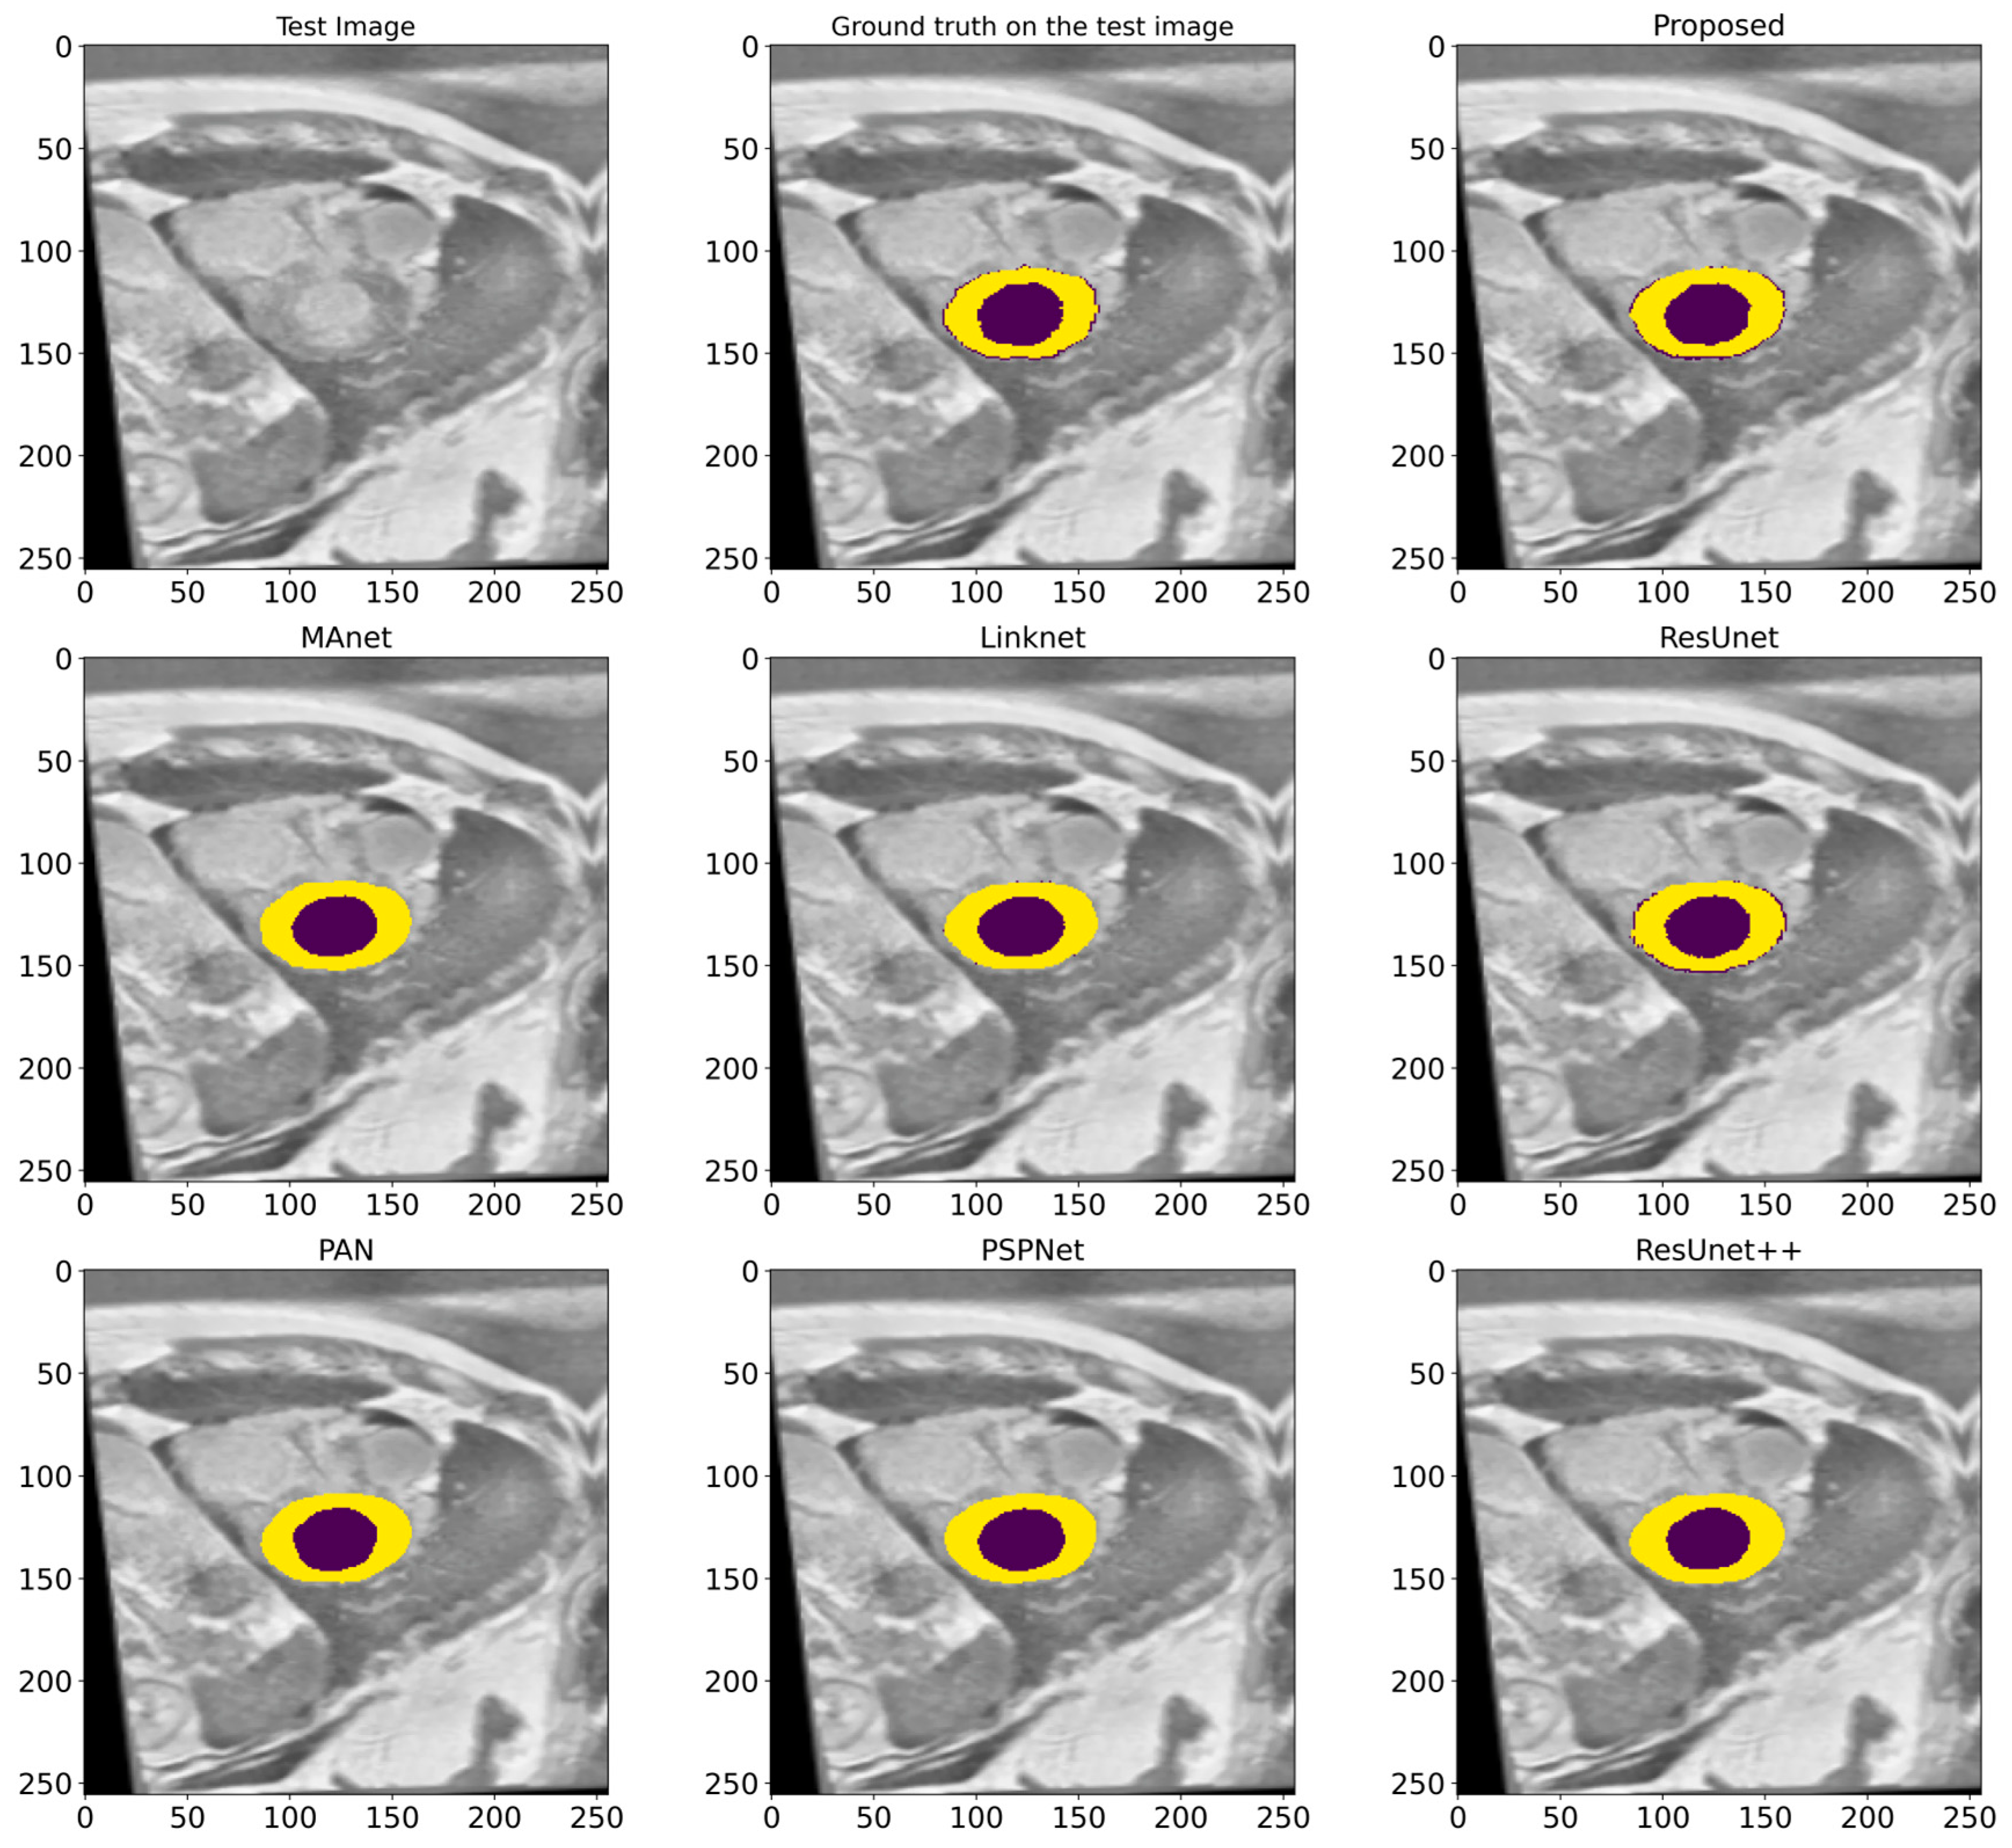

In this work, a comparative evaluation of the performance of the proposed model with six other SOTA deep segmentation models was carried out to demonstrate its superiority over its analogs. Figure 10 provides a qualitative comparison of segmentation results produced by various models against the ground truth. The proposed model demonstrates the highest visual accuracy, closely aligning with the manual annotations for both the LV and Myo regions. ResUnet also performs well, showing smooth and spatially coherent boundaries, although with slightly less precision than the proposed model. In contrast, models such as PAN, PSPNet, and ResUnet++ tend to over-segment the Myo area, while others like MAnet and LinkNet display a moderate agreement with the ground truth. These visual results support the effectiveness of the proposed architecture in capturing detailed anatomical structures more reliably than existing approaches. Table 2 provides more evaluation metrics, such as the Recall, Dice, precision, and F1-score, that allow for a thorough comparison of the performance of different models. The visualization of these metrics is presented in Figure 11, which enables us to demonstrate their comparison. The analysis of the results showed that the proposed model not only outperforms other modern models in most metrics but also demonstrates stable results on various datasets, which indicates its versatility and reliability. Table 2 shows that our model demonstrates superiority over the best SOTA segmentation model (MAnet []). Specifically, it outperforms MAnet by an IoU of 2.2%, a Recall of 2.88%, a Dice of 1.24%, and an F1-score of 1.24%. These results confirm the high efficiency and accuracy of the proposed model, making it superior not only to MAnet but also to the other six SOTA segmentation models. The very small standard deviation values indicate that our model performs well across all batches and proves the stability of the model’s performance. The results in Table 2 demonstrate the effectiveness of the proposed enhancements, reflecting clear improvements in the segmentation performance. The higher rates of Recall and precision indicate that our model can more effectively identify and classify objects in images and minimize the number of missed objects (false negatives) and misclassified objects (false positives). These findings indicate the value of our study and the development of the proposed approach; moreover, these results confirm the excellence of our model and indicate its potential for applications in various practical contexts where precise segmentation is critical. Therefore, the proposed model can provide a foundation for future research and development in image segmentation.

Figure 10.

A visualized comparison of predictions of different deep segmentation models. The LV is marked in the deep violet color, and the Myo is highlighted in yellow.